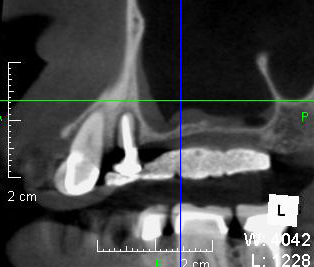

CT検査をしてみると,確かにインプラントを埋入したい部位に骨が全然無い(CT上で黒く映っている)のが分かります。

サイナスリフト手術の6ヶ月後のCTです。以前は骨が無く黒く映っていたところに骨が出来て(白く映って)いるのが分かります。